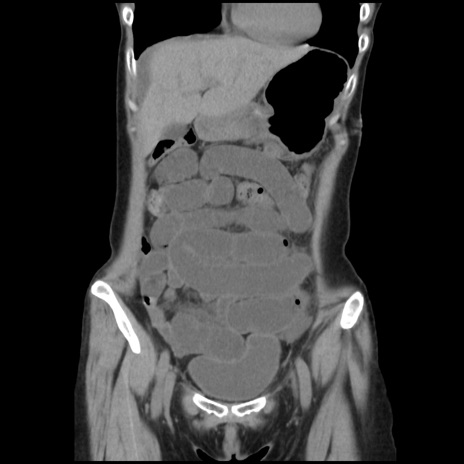

横断像